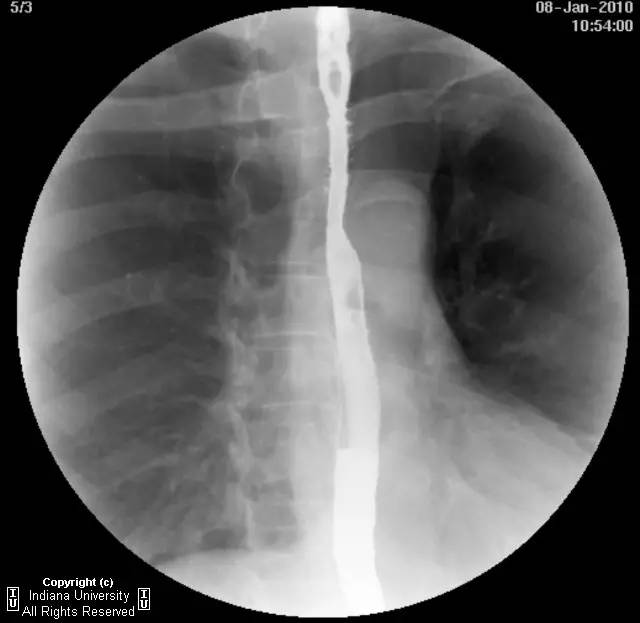

【影像学表现】下咽部正常,环咽肌功能正常。颈段食管无外生性病变压迫或异常扩张。胸中段食管长节段狭窄,逐渐移行为正常食管粘膜。大量小的烧饼样钡斑位于相应食管外呈浮萍样,与食管管腔无直接交通。稠或稀钡剂通过均无延迟。1cm钡剂片延迟通过,约30分钟后自动溶解。余食管动力正常。

【诊断】食管壁内假性憩室并长节段狭窄

Long segmentstricture with esophageal intramural pseudodiverticulosis